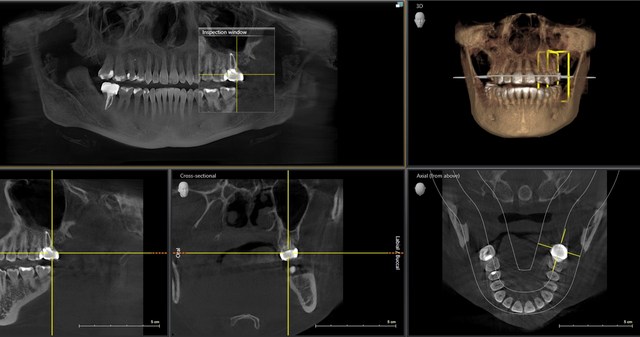

We use cutting-edge ceramic implant technology for superior biocompatibility.

Metal-free, biocompatible ceramic implants that integrate naturally with your jawbone.